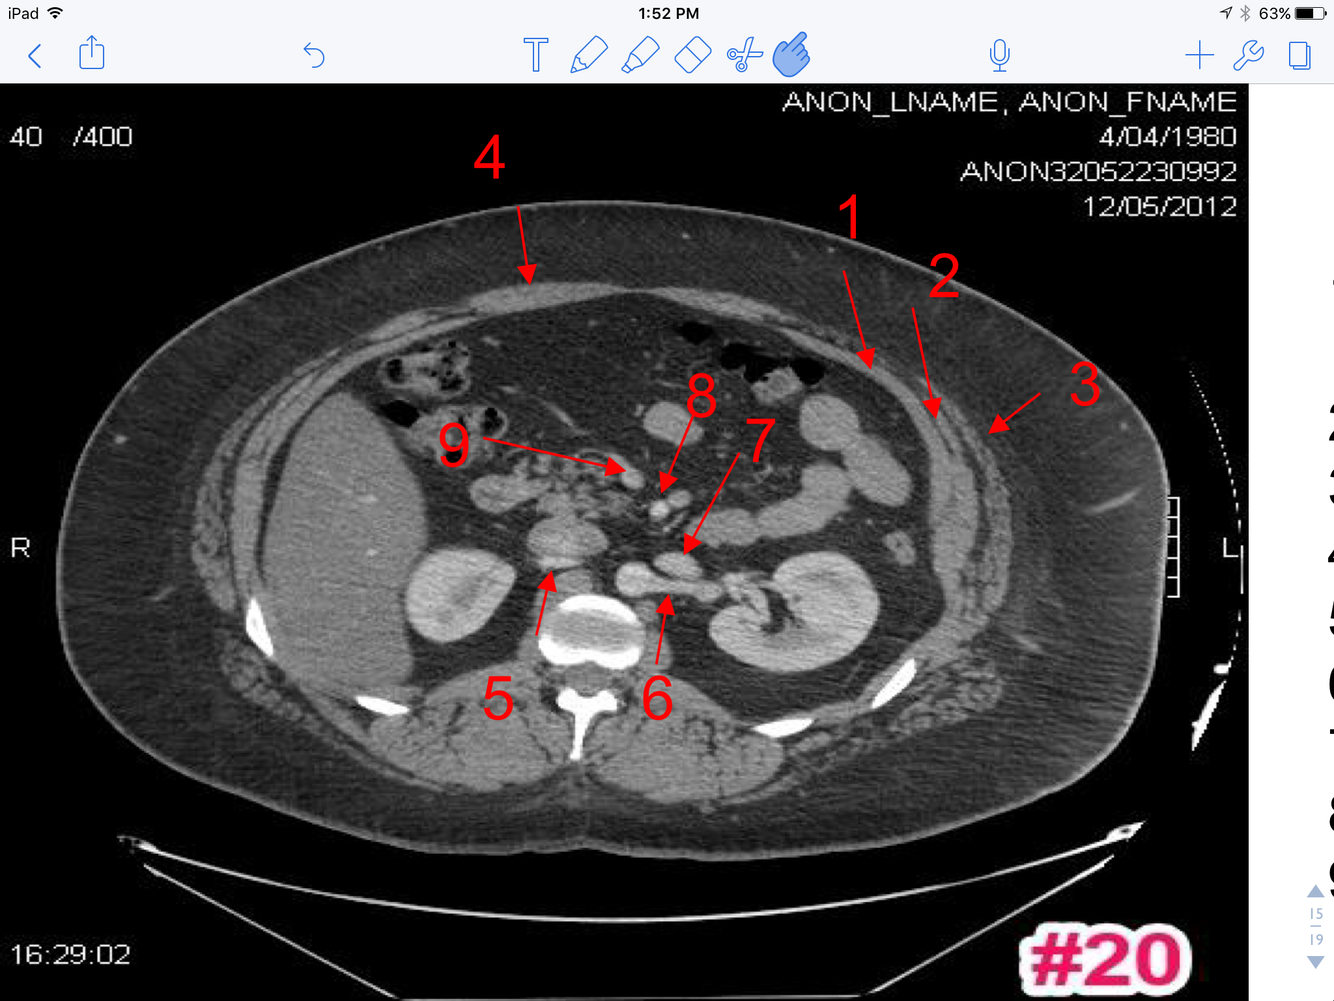

13

Q

A

1. Transversus abdominus muscle

2. Lt. Internal abdominal oblique M

3. Lt. External abdominal oblique M

4. Rectus Abdominus

5. Rt. Renal A

6. Lt. Renal A

7. Lt. Renal V

8. Superior mesenteric A

9. Superior mesenteric V